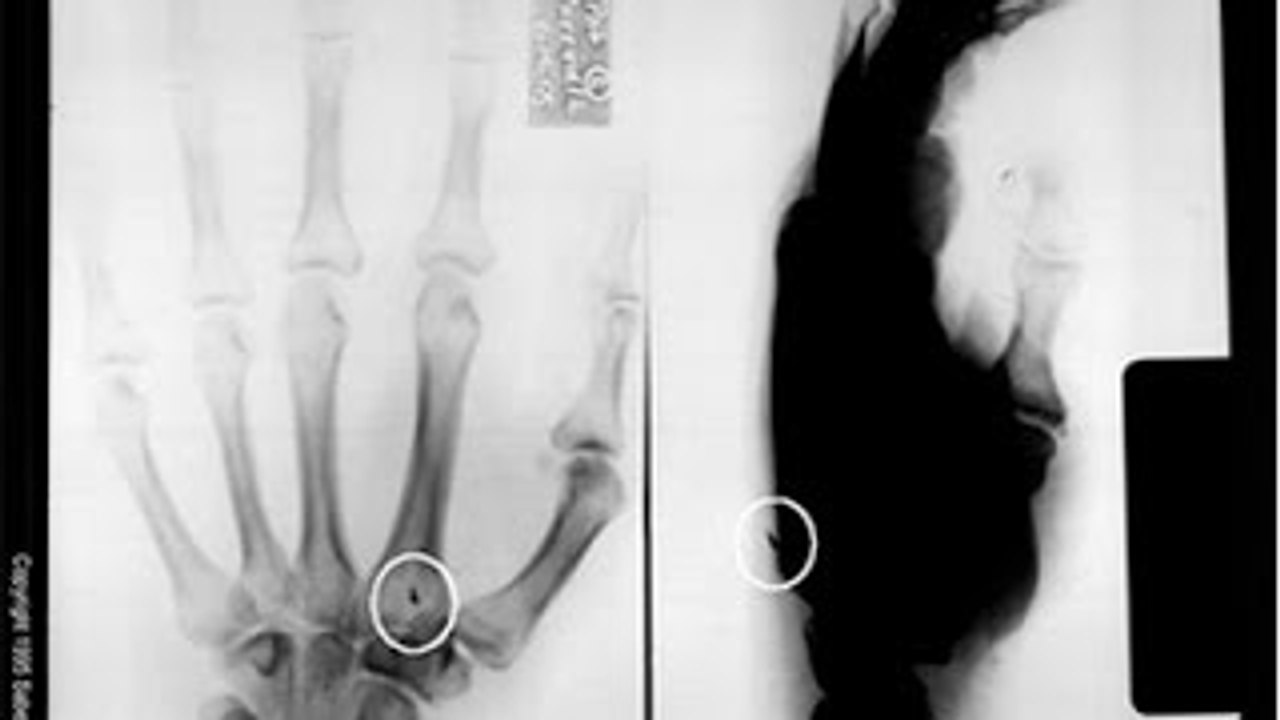

<br />Le 7 août 1998, un groupe de terroristes fait exploser un camion piégé à proximité de l'ambassade des Etats-Unis de Nairobi, capitale du Kenya. Le même jour, quasiment à la même heure, une attaque similaire est perpétrée contre l'ambassade américaine de Dar es Salaam, le centre économique de la Tanzanie. Plus de 250 personnes, dont douze Américains, ont trouvé la mort dans ces attentats, qui ont été, par la suite, attribués à l'organisation terroriste Al-Qaida.